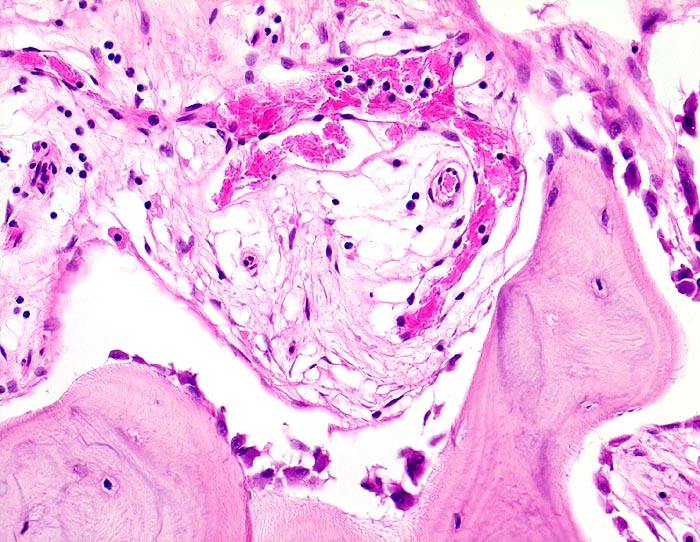

• Riesenosteoklasten mit über 20 Kernen sind an der Knochenoberfläche erkennbar.

• Vermehrte kubische aktive Osteoblasten bauen Knochen an.

• Lockere Markfibrose.